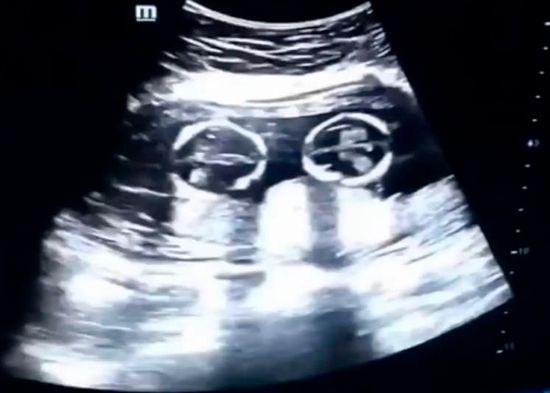

Una ecografía capta la 'pelea' entre dos gemelas en el vientre de su madre

REDACCIÓN INTERNACIONAL.- El video de una ecografía realizada en Yinchuan (Ningxia, China) en la que se ve a dos hermanas gemelas ‘peleándose’ dentro del vientre de su madre, se ha vuelto viral desde que este lunes apareciera en las redes sociales.

En la grabación, realizada por el padre el pasado mes de diciembre, se observa la pugna de los fetos, de tan solo cuatro meses, que parecen sacudirse patadas y puñetazos.

Se trata de un extraño tipo de embarazo de riesgo en el que las gemelas comparten saco amniótico y placenta dentro del útero. Las dos nacieron sanas el pasado 8 de abril mediante cesárea.